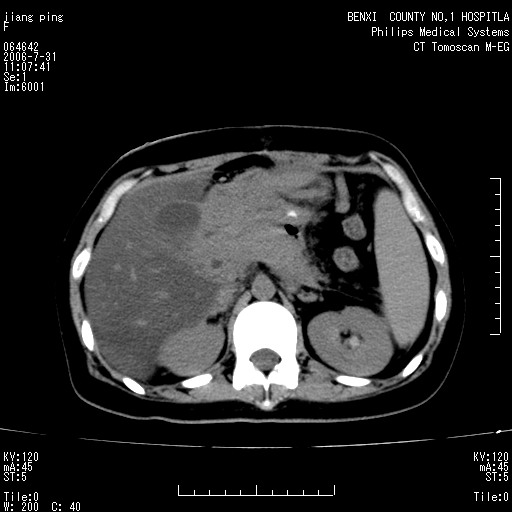

以下是引用晓杰在2006-8-1 9:01:00的发言:[br]支持营养不良导致脂肪肝。[br]胰头增大界限不清,考虑为胰腺炎破坏十二指肠粘膜、肠壁增厚、肠腔狭窄,并与胰头粘连所致

以下是引用jiajie在2006-7-31 20:34:00的发言:[br]支持营养不良导致脂肪肝。[br]胰头增大界限不清,考虑为胰腺炎破坏十二指肠粘膜、肠壁增厚、肠腔狭窄,并与胰头粘连所致。